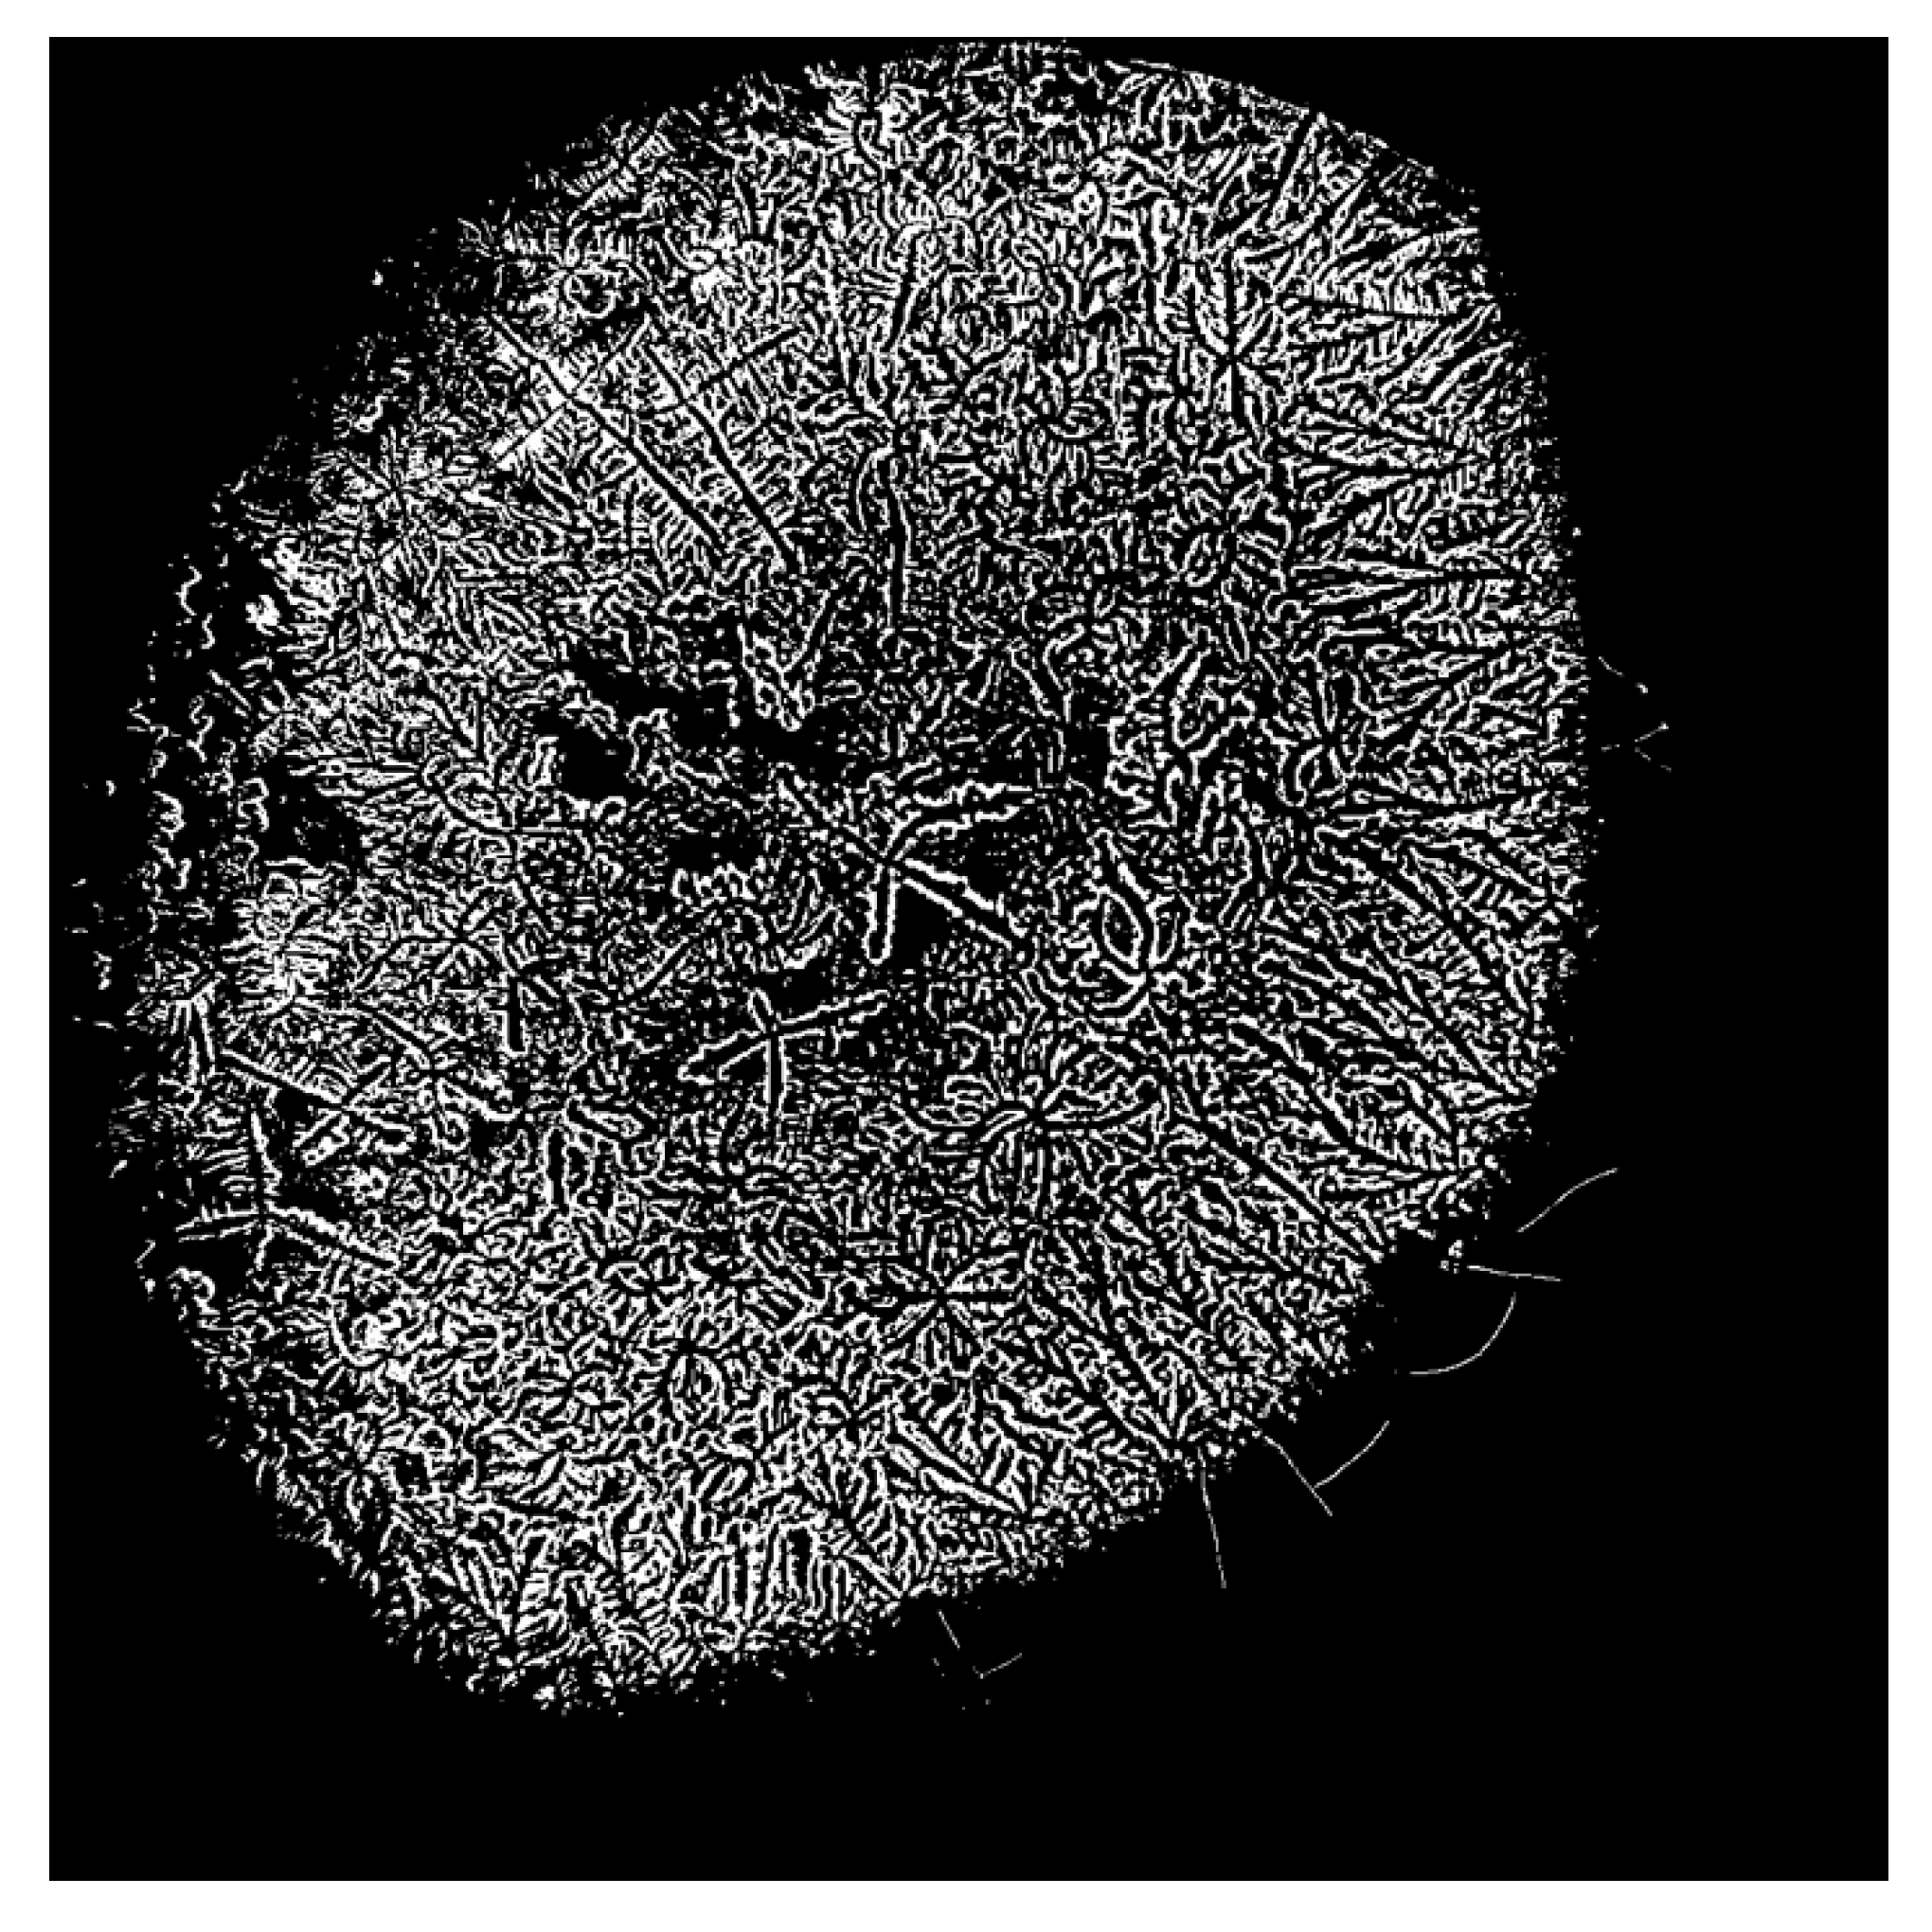

- Masmali, A.M.; Murphy, P.J.; Purslow, C. Development of a new grading scale for tear ferning. Contact Lens Anterior Eye 2014, 37, 178–184. [Google Scholar] [CrossRef]

- Masmali, A.M.; Purslow, C.; Murphy, P.J. The tear ferning test: A simple clinical technique to evaluate the ocular tear film. Clin. Exp. Optom. 2014, 97, 399–406. [Google Scholar] [CrossRef] [PubMed]